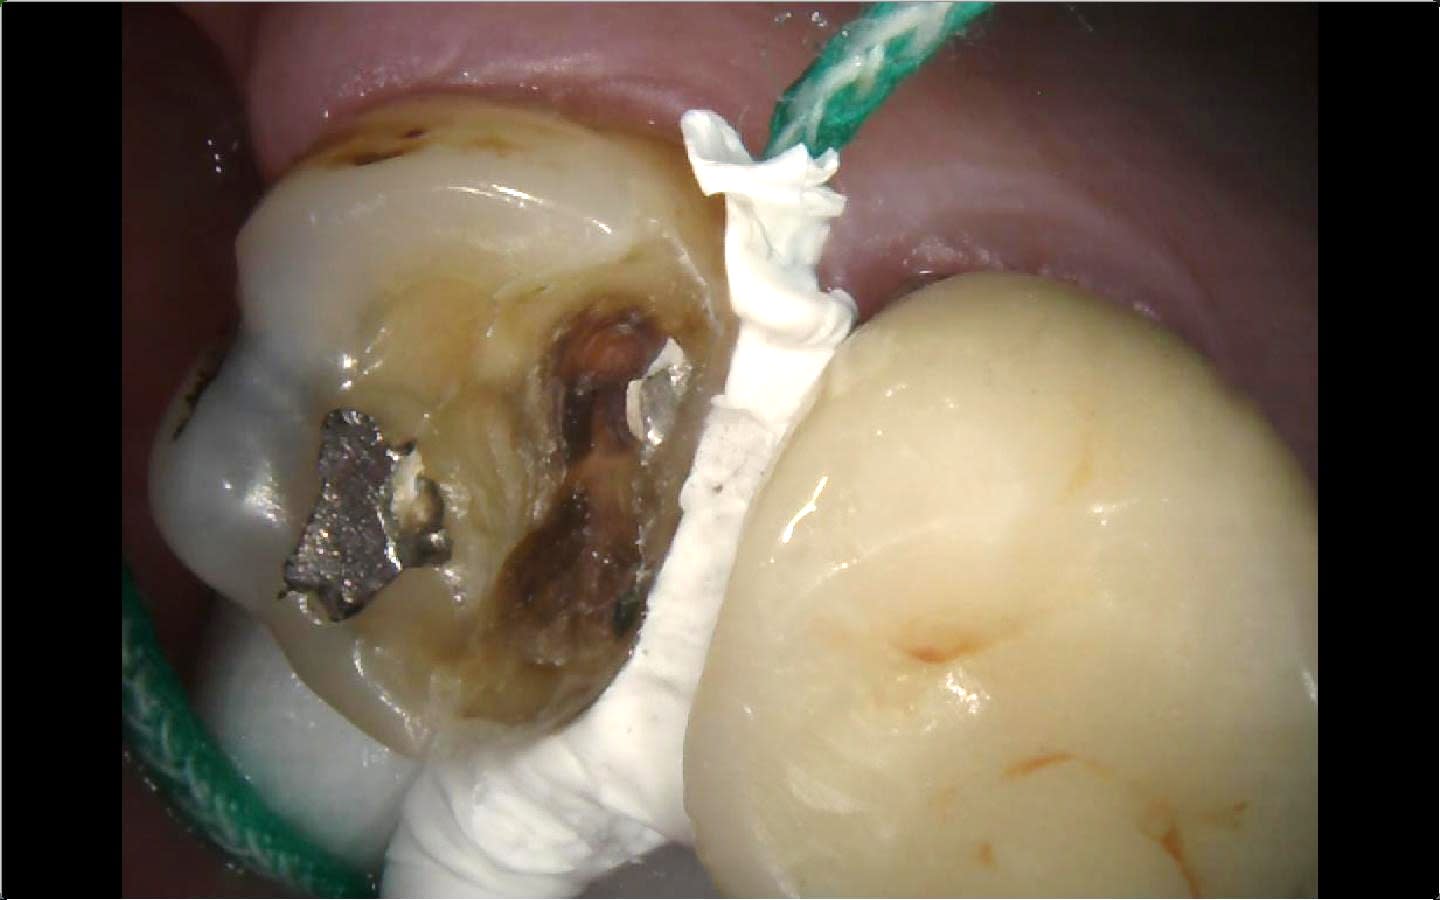

Ah oui c’est pas con ça empêche le sang de remonter ton truc ou ça empêche le fluide gingival de remonter . Ça fait comme un joint. Tiens gros overlay en compo sur 36

0c636acc 4624 4f32 b7a8 90d653a38b72 aw7yqn - Eugenol